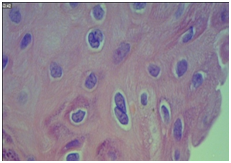

The histopathological slides were revised under multi-head microscopes in order to classify the histological type of the lesion, its differentiation, and also to verify the presence or absence of characteristic HPV (koilocyte) histological stigmas. In HE, CECCP were cataloged as "Keratinized", when they presented corneal pearl and individual keratinization; "Non-Keratinized" when they did not show signs of keratin production; and "Mixed", when the areas that had both characteristics were present. Identification of koilocytes was characterized by cells of the intermediate or superficial stratum of the epithelium, with well-marked cytoplasm clear halo and nuclear atypia (Figure 1).

Figure 1 Coilocyte in squamous neoplasia.

Note: Photomicrography demonstrating koilocyte (arrow) in squamous neoplasia. Hematoxylin-Eosin 400x magnification.